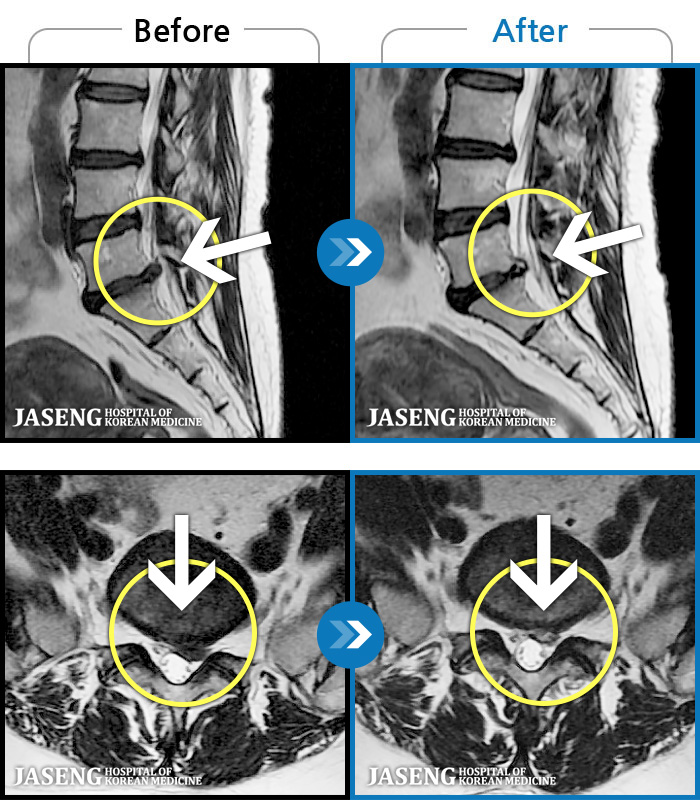

MRI ġ

1,301 MRI ũ ʸ Ȯϼ.